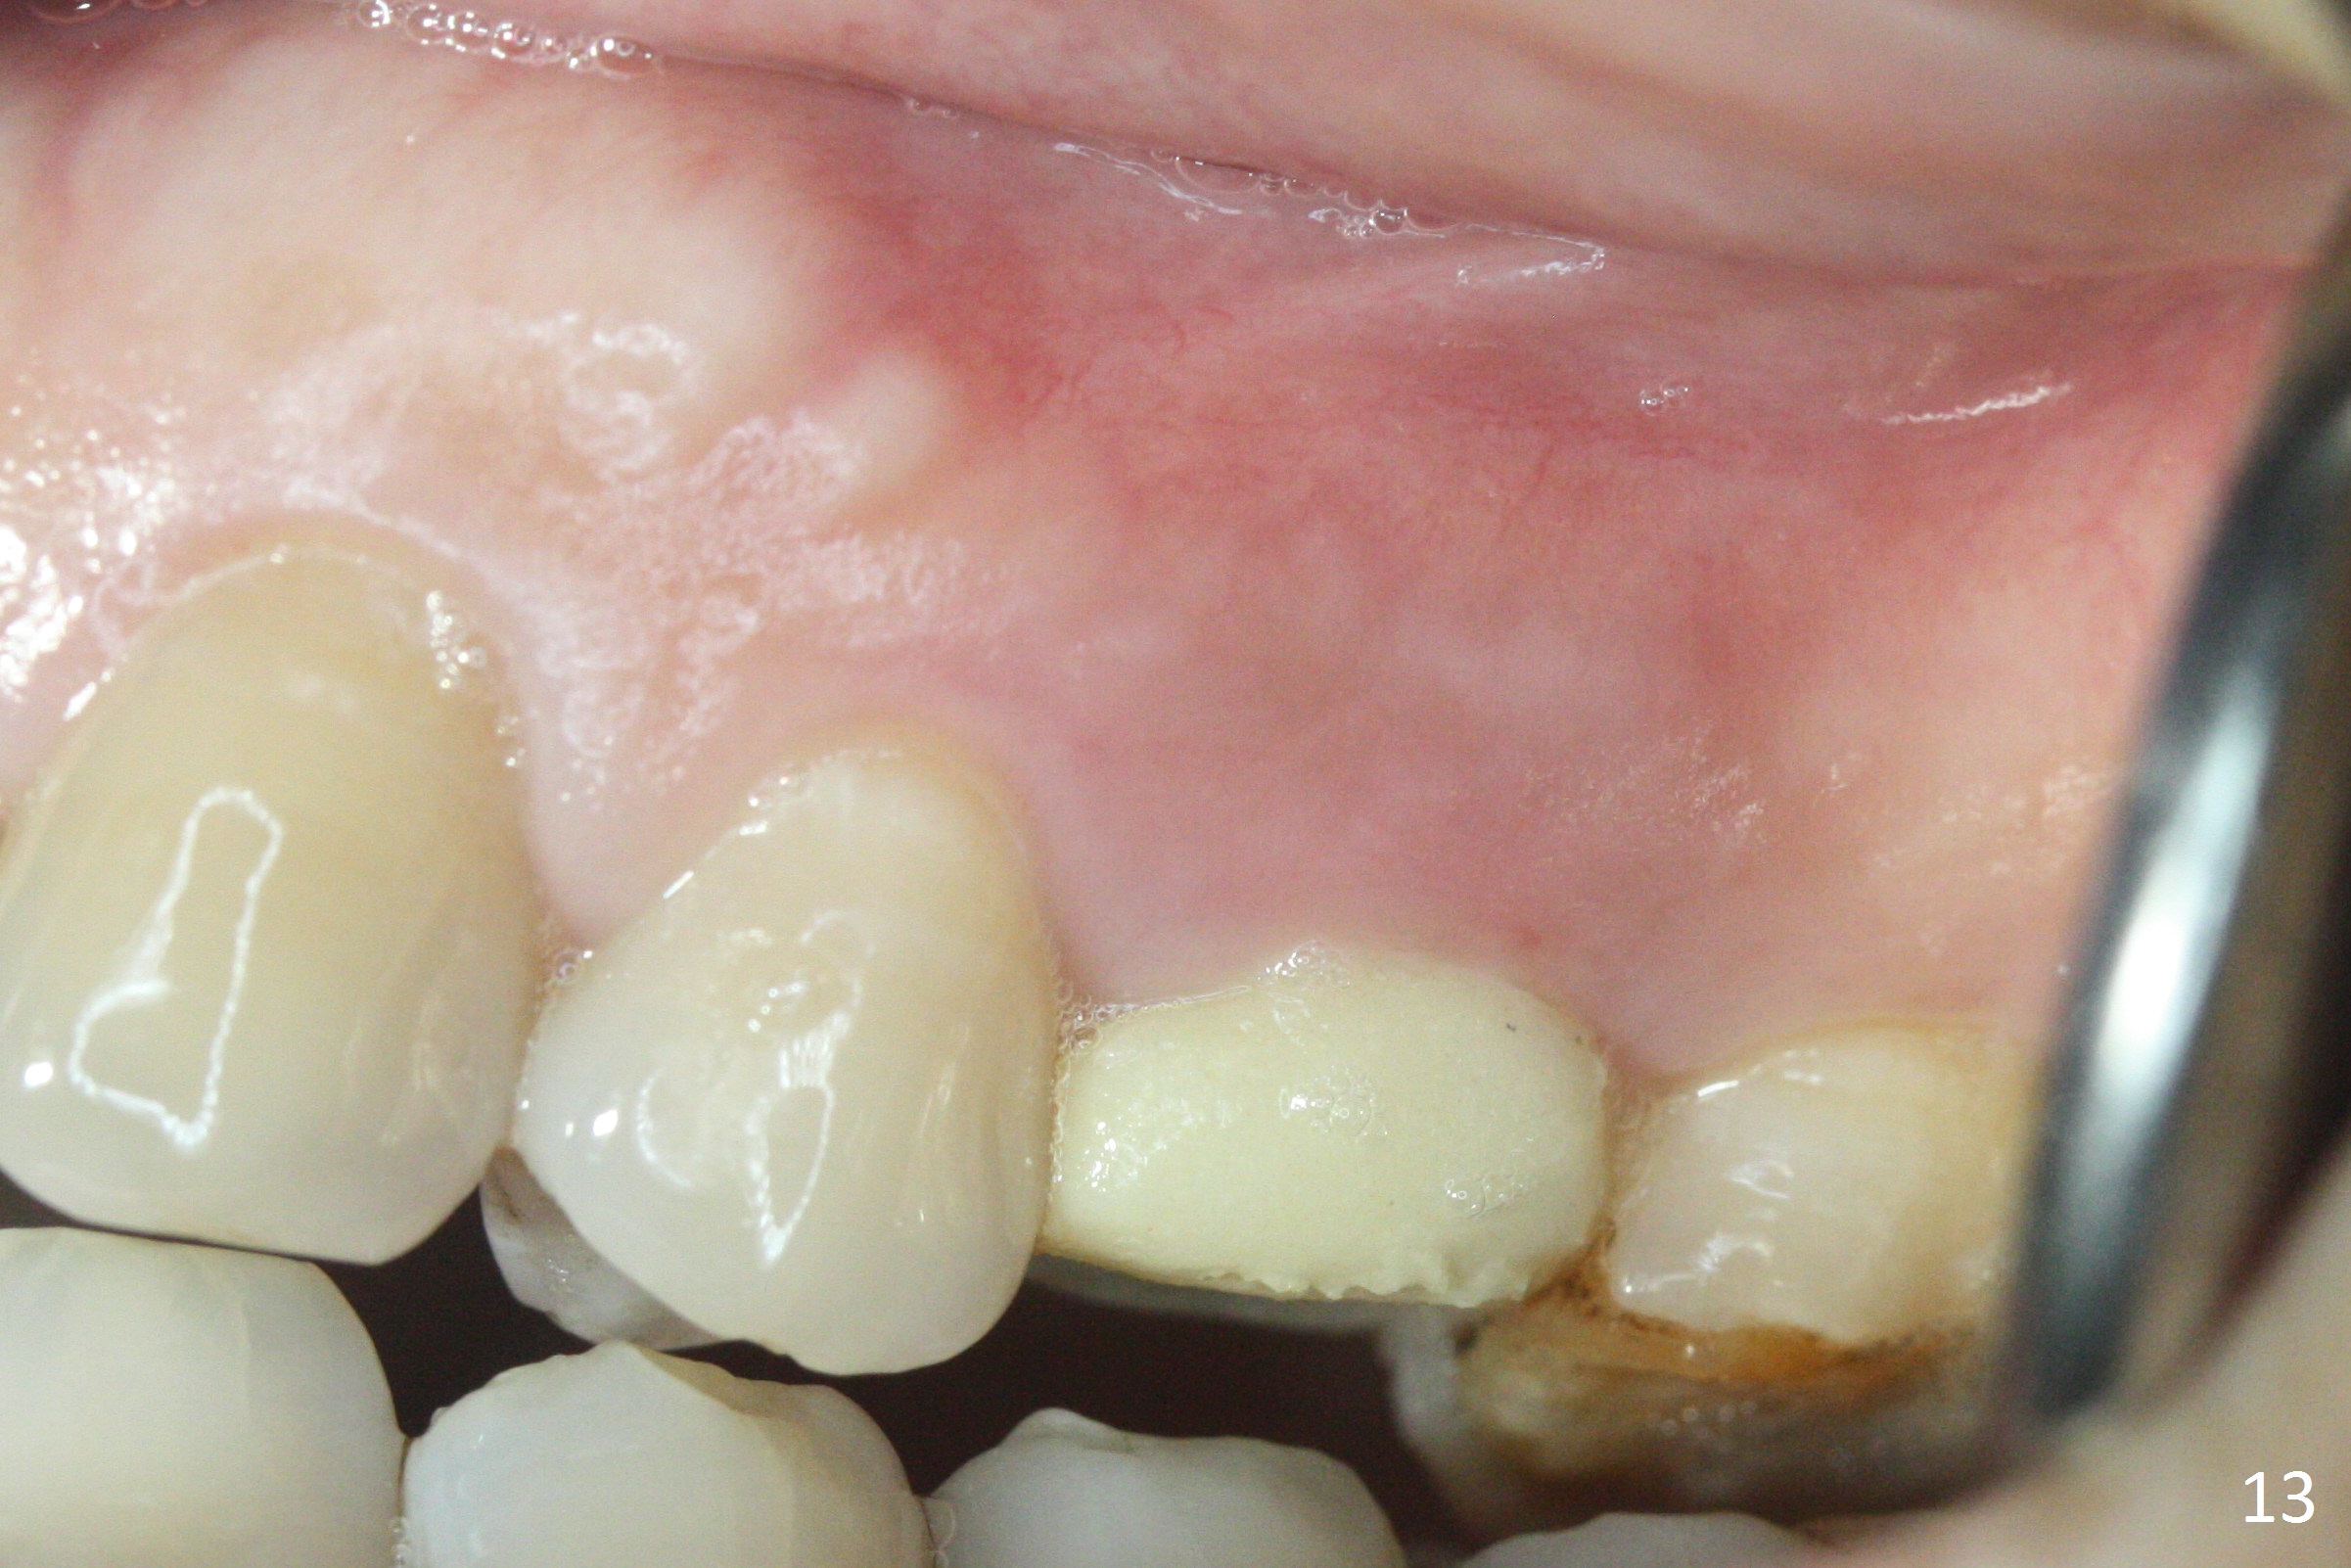

The buccal gingival inflammation subsides 1 week postop (Fig.13,14). There is no bone loss 4 months postop (Fig.15,16). The crown is recemented 6 months post cementation (probably due to short abutment); there is a residual cement (Fig.17 <), which is removed (Fig.18).